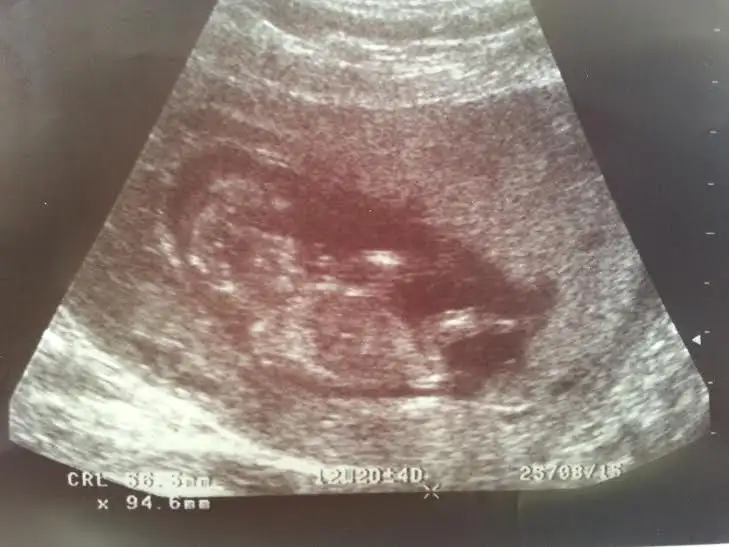

dr soylemeden siz gorun genital nub teorisi ( bebegin cinsiyeti)

• CAM00163.webp

CAM00163.webp

19,8 KB · Görüntüleme: 127